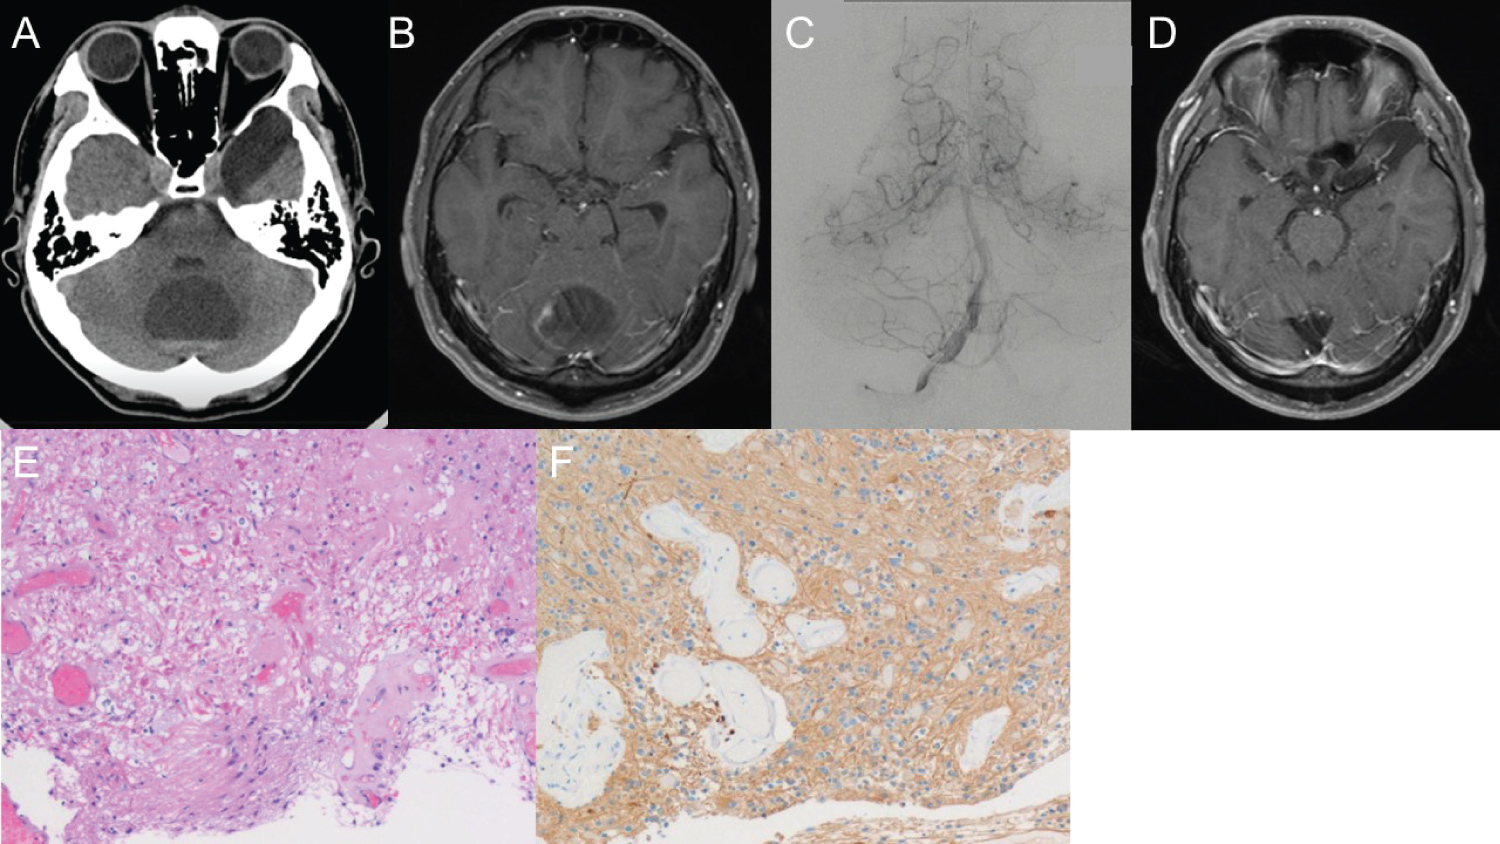

A 25-year-old man with intellectual disabilities and left-sided hemiparesis presented to our department with progressive right parieto-temporal head puffing. On examination, he also showed communication disability and left hemi-spatial neglect. Head computed tomography (CT) and brain magnetic resonance imaging (MRI) revealed multiple cystic solid tumors in the right temporal, parietal, and occipital regions with a midline shift (Figure 1A and Figure 1B). A carotid angiogram of the right side revealed multiple arterial feedings from the right middle cerebral artery, right tentorial artery, and branches of the middle meningeal artery (Figure 1C, Figure 1D and Figure 1E). Neuronavigation-guided gross total resection (GTR) was performed (Figure 1F, Figure 1G and Figure 1H). Histopathological examination revealed an APA with varying proportions of compacted bipolar cells and loose microcystic areas (Figure 2A, Figure 2B and Figure 2C). We observed numerous eosinophilic granular bodies and rare mitotic figures. The tumor cells were positive for GFAP (Figure 2D) and negative for CD34, p53, and IDH-1. ATRX was absent in the tumor cell nuclei. The Ki-67 index was approximately 1%, and the modified Rankin Scale (mRS) score was comparable before and after the operation.

Figure 1: Images and intraoperative findings of Case 1.

Initial head computed tomography (CT) (A) and brain magnetic resonance imaging (MRI) (B) show multiple cystic solid tumors in the right temporal, parietal, and occipital regions with midline shift. A carotid angiogram of the right side (C: Anterior-posterior view, D: Lateral view) reveals multiple arterial feedings from the right middle cerebral artery and right tentorial artery. The right external carotid angiogram (E) shows tumoral feeding from the branches of the middle meningeal artery. Intraoperative findings show a thick, vascular-rich tumor wall and cyst (F). Neuronavigation-guided surgical gross total resection postoperative images (G: MRI; H: Head CT). View Figure 1

Figure 2: Pathological findings of Case 1.

Histopathological examination in Case 1 revealed a pilocytic astrocytoma with varying proportions of microcystic areas (A), compacted bipolar cells, and loose microcystic areas (B). There are numerous eosinophilic granular bodies and rare mitotic figures (C). The tumor cells are positive for GFAP (D). View Figure 2